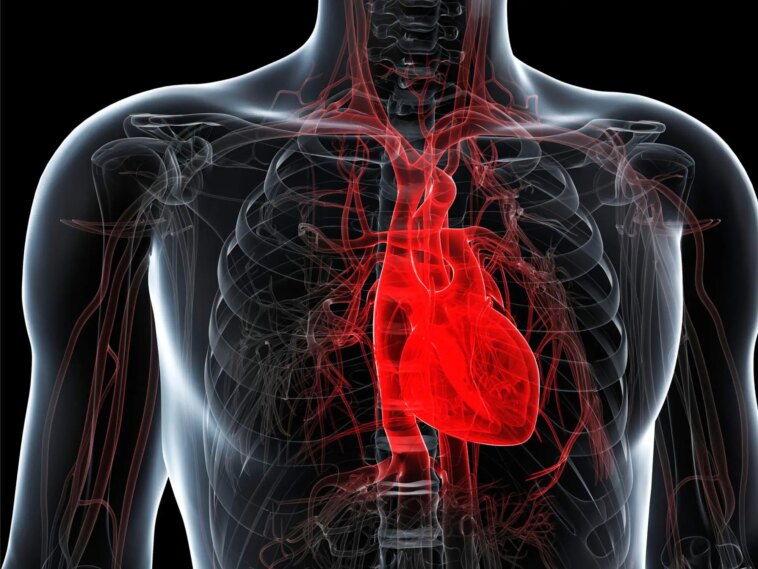

Partout où les scientifiques ont recherché des microplastiques, ils ont découvert leur présence : dans notre nourriture, notre eau, notre air et même dans certaines parties du corps humain. Cependant, l’examen de nos organes les plus internes, qui ne sont pas directement exposés à l’environnement, reste limité. Une nouvelle étude pilote impliquant des personnes ayant subi une chirurgie cardiaque révèle que les microplastiques sont présents dans de nombreux tissus cardiaques. L’étude, récemment publiée dans la revue Sciences et technologies environnementales rapporte également des preuves suggérant que des microplastiques ont été introduits de manière inattendue au cours des procédures.

Dans une expérience pilote, les chercheurs ont collecté des échantillons de tissus cardiaques auprès de 15 personnes lors d’opérations cardiaques, ainsi que des échantillons de sang avant et après l’opération auprès de la moitié des participants. Ensuite, l’équipe a analysé les échantillons par imagerie infrarouge directe au laser et a identifié des particules de 20 à 500 micromètres de large composées de huit types de plastique, dont le polyéthylène téréphtalate, le chlorure de polyvinyle et le poly(méthacrylate de méthyle).

Cette technique a détecté des dizaines, voire des milliers de morceaux de microplastiques individuels dans la plupart des échantillons de tissus, bien que les quantités et les matériaux variaient selon les participants. Tous les échantillons de sang contenaient également des particules de plastique, mais après l’intervention chirurgicale, leur taille moyenne a diminué et les particules provenaient de types de plastiques plus divers.

Bien que l’étude ait compté un petit nombre de participants, les chercheurs affirment avoir fourni des preuves préliminaires selon lesquelles divers microplastiques peuvent s’accumuler et persister dans le cœur et ses tissus les plus internes. Ils ajoutent que les résultats montrent à quel point les procédures médicales invasives constituent une voie négligée d’exposition aux microplastiques, offrant un accès direct à la circulation sanguine et aux tissus internes. D’autres études sont nécessaires pour comprendre pleinement les effets des microplastiques sur le système cardiovasculaire d’une personne et son pronostic après une chirurgie cardiaque, concluent les chercheurs.